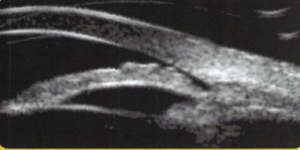

UBM : échographie à haute fréquence pour affiner l’analyse de l’angle dans certains cas.

Lorsque ce geste ne suffit pas à obtenir les effets escomptés après une iridotomie, un UBM est nécessaire pour analyser la partie inaccessible lors de l’examen clinique située en arrière de l’iris comme le corps ciliaire.